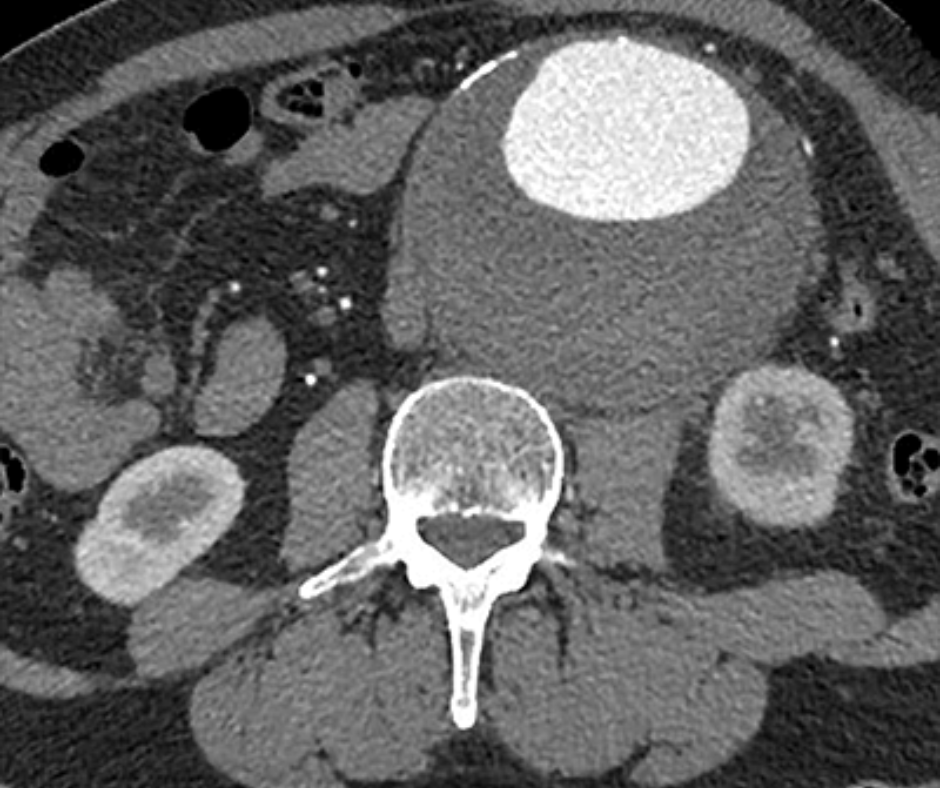

In a study involving 201 consecutive patients presenting to emergency departments (EDs) with abdominal pain, researchers found that radiology faculty accuracy rates in interpreting non-contrast, abdominopelvic computed tomography (CT) scans ranged from 68 to 74 percent.